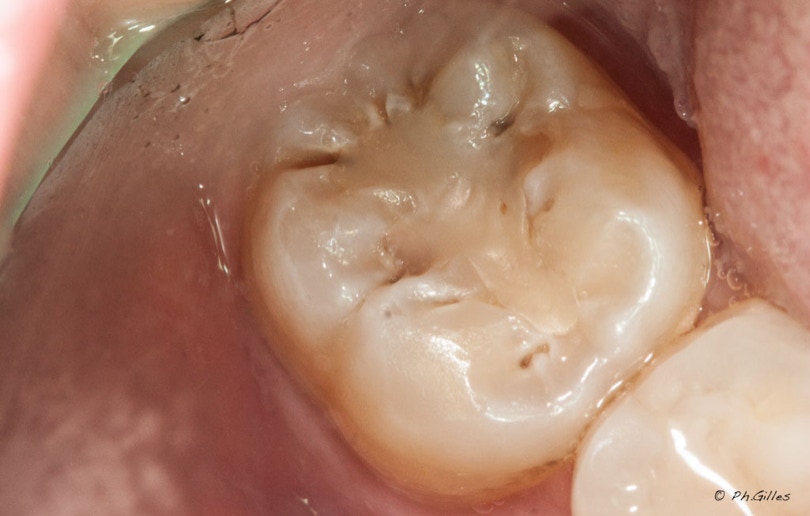

Avant - Détecteur de carie - Après